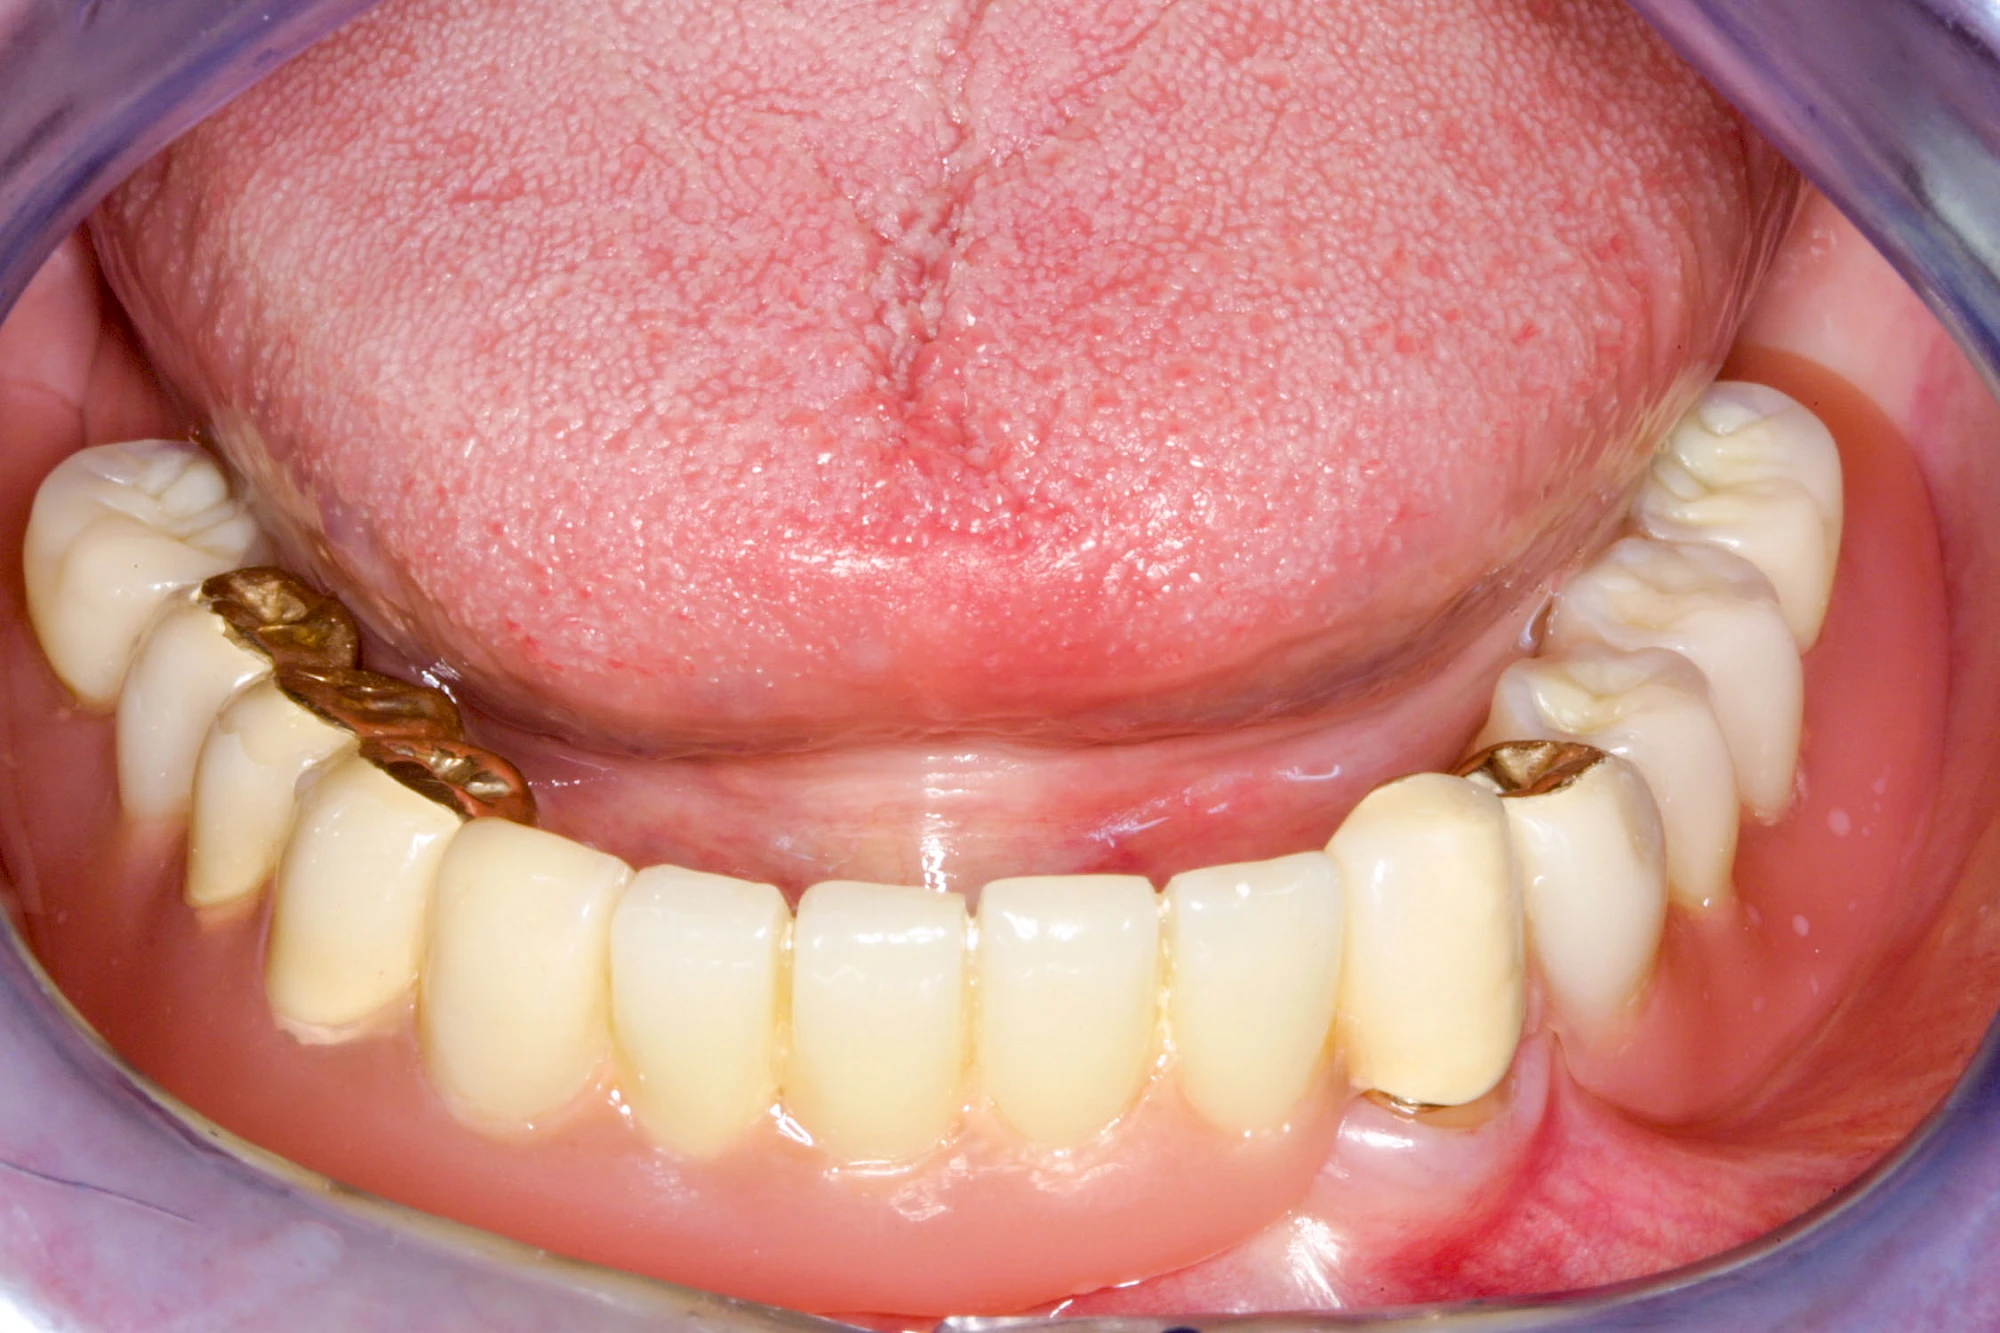

Bei herausnehmbaren Prothesen werden Implantate eingesetzt, um den Halt und den Tragekomfort der Prothesen zu verbessern. Dazu kommen verschiedene Verbindungselemente zum Einsatz:

- Teleskope

- Kugelköpfe

- Tellerförmige Lokatoren

- Stege

- Magnete (selten)

Neben rein implantat-getragenen zahnärztlichen Versorgungen werden bei herausnehmbaren Prothesen Implantate auch in Sinne einer "strategischen Pfeilervermehrung" ergänzend zu eigenen Zähnen zur Verankerung eines Zahnersatzes genutzt.

Varianten zur Verankerung von abnehmbarem Zahnersatz auf Implantaten